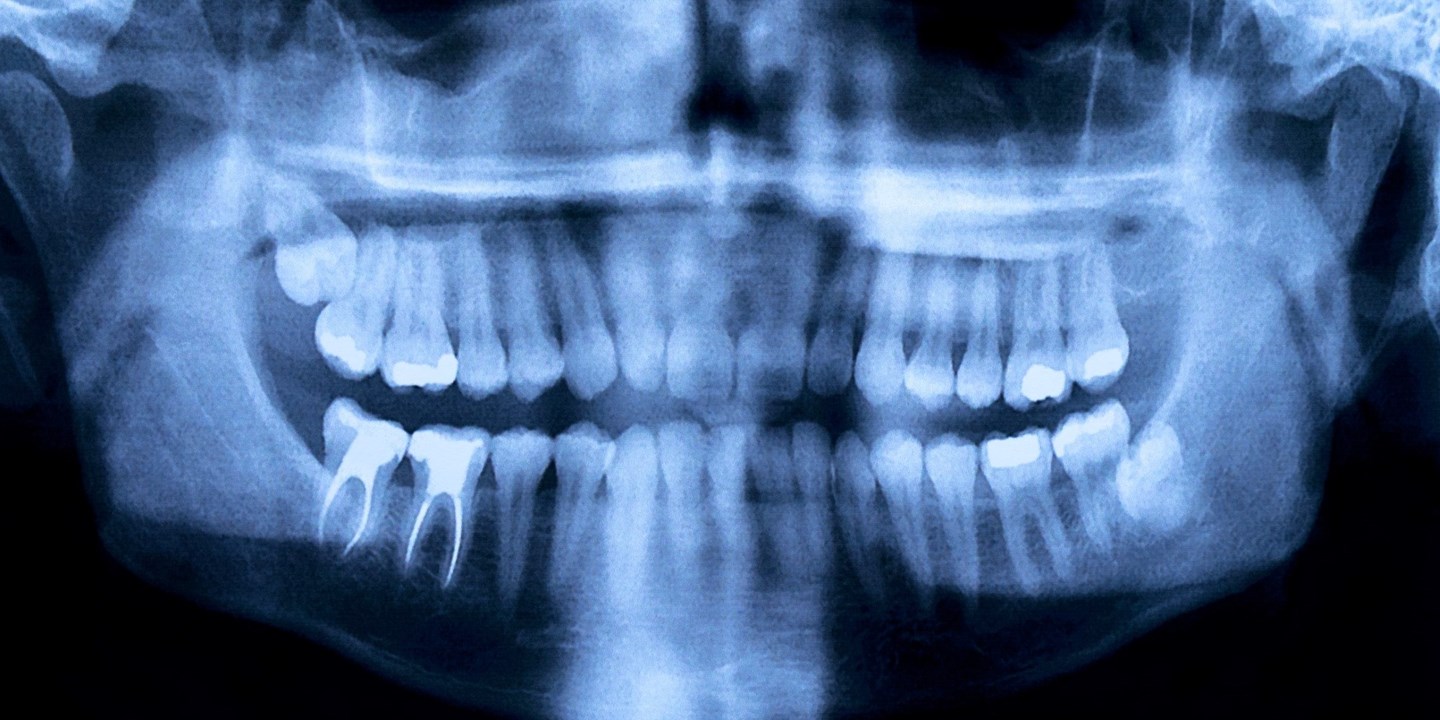

Rotfyllning

Det finns flera orsaker till att pulpan inuti tanden dör, bland annat karies, läckande fyllningar och tandgnissling.

En inflammation eller infektion inne i tanden innebär att pulpan är skadad. Besväras du av molande värk, känslighet för kyla och värme, svullnad och ömhet kan det vara tecken på en skadad pulpa.

Det är dock inte alltid du får symptom. En levande pulpa är förstås att föredra, men tanden går att rädda även om pulpan skulle dö. Lösningen är rotbehandling.